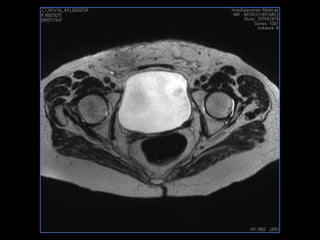

PROTOCOLO pelvis SAG T2, Y FAT SAT (FINOS) AXIAL T1  AX FAT SAT CON   GADOLINIO :  AX T1 Y COR T1 SAT: NO  FASE: RL THK: 3MM  COIL:  GAP: (FACTOR 1.4) 1MM FOV: 40 CM NEX:2 SINCRONIZACION RESPIRATORIA EN 3 O 4 CICLOS ALE

resonancia de abdomen